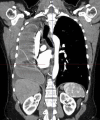

Postpneumonectomy syndrome (PPS) is a rare complication after pneumonectomy characterised by severe mediastinal shift leading to airway compression and respiratory distress. We present a case of a woman in her mid-40s who developed PPS following a right pneumonectomy for bronchial mucoepidermoid carcinoma. Surgical treatment of PPS had not previously been performed in Denmark by Danish surgeons, which is why we consulted with a British surgeon. The surgery was performed in Denmark.The procedure resulted in immediate respiratory improvement, and the patient was discharged 22 days postoperatively. Follow-up demonstrated sustained airway patency and no signs of cancer recurrence. This case highlights the feasibility and effectiveness of surgical management of PPS in centres with limited prior experience and supports mediastinal repositioning with prosthetic implants as a viable treatment option in severe cases.